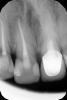

Marina_A Опубликовано 29 мая, 2013 Автор Поделиться Опубликовано 29 мая, 2013 (изменено) недопак все-таки был канала дополнительного я не нашла ( то ли что-то не так с КТ, то ли с моей эндодонтией)))посмотрим, что дальше будет. думаю, стоит влезть в 12, 21, переделать кт, и если ниче не прояснится, отправлять к кому-то другому any ideas? Изменено 29 мая, 2013 пользователем M. Antoniuk Ссылка на комментарий

ger_berra Опубликовано 29 мая, 2013 Поделиться Опубликовано 29 мая, 2013 (изменено) фотография.JPG недопак все-таки был канала дополнительного я не нашла ( то ли что-то не так с КТ, то ли с моей эндодонтией)))посмотрим, что дальше будет. думаю, стоит влезть в 12, 21, переделать кт, и если ниче не прояснится, отправлять к кому-то другому any ideas? Отличная "пуговка"!Боль прошла?Замечательно,что Вам удалось сохранить констрикцию! Изменено 29 мая, 2013 пользователем ger_berra Ссылка на комментарий